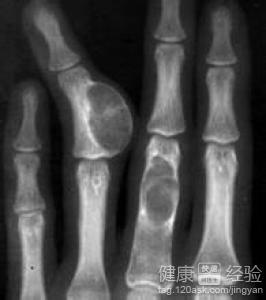

骨癌片子

骨癌的早期小肿块图片

骨癌是什么样子的图片

骨癌图片高清图片

骨癌的早期症状图

骨癌骨头图片

骨癌图片